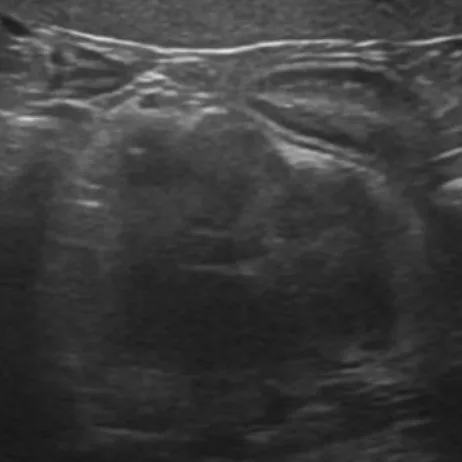

腹部超音波検査

副腎の評価(サイズや形)、血管との関連性を行います。